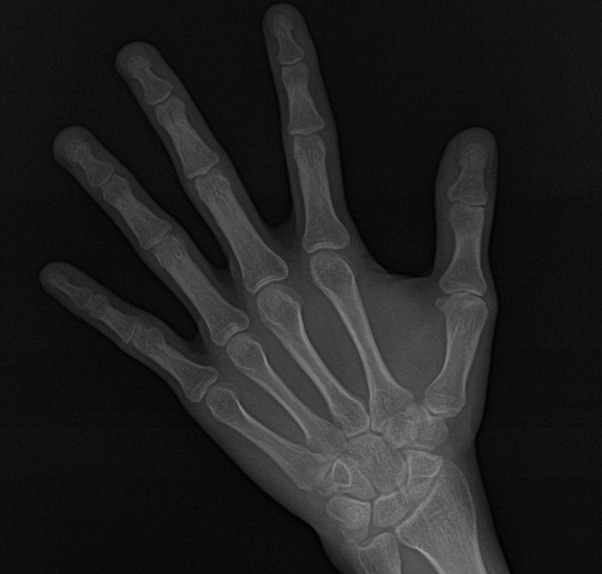

手根骨撮影